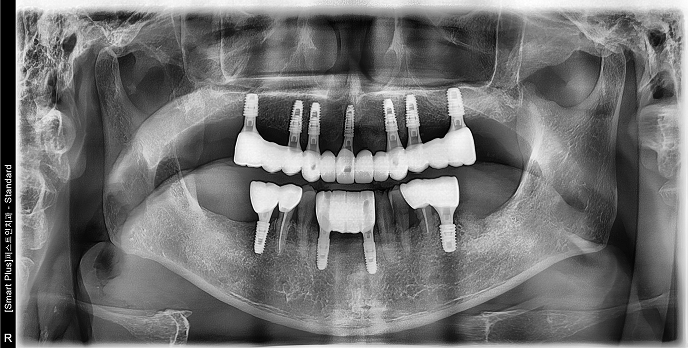

• 70대 남성 | 치주염 | 임플란트 | 치료기간 4개월

Before 2024.12.06

After 2025.04.11